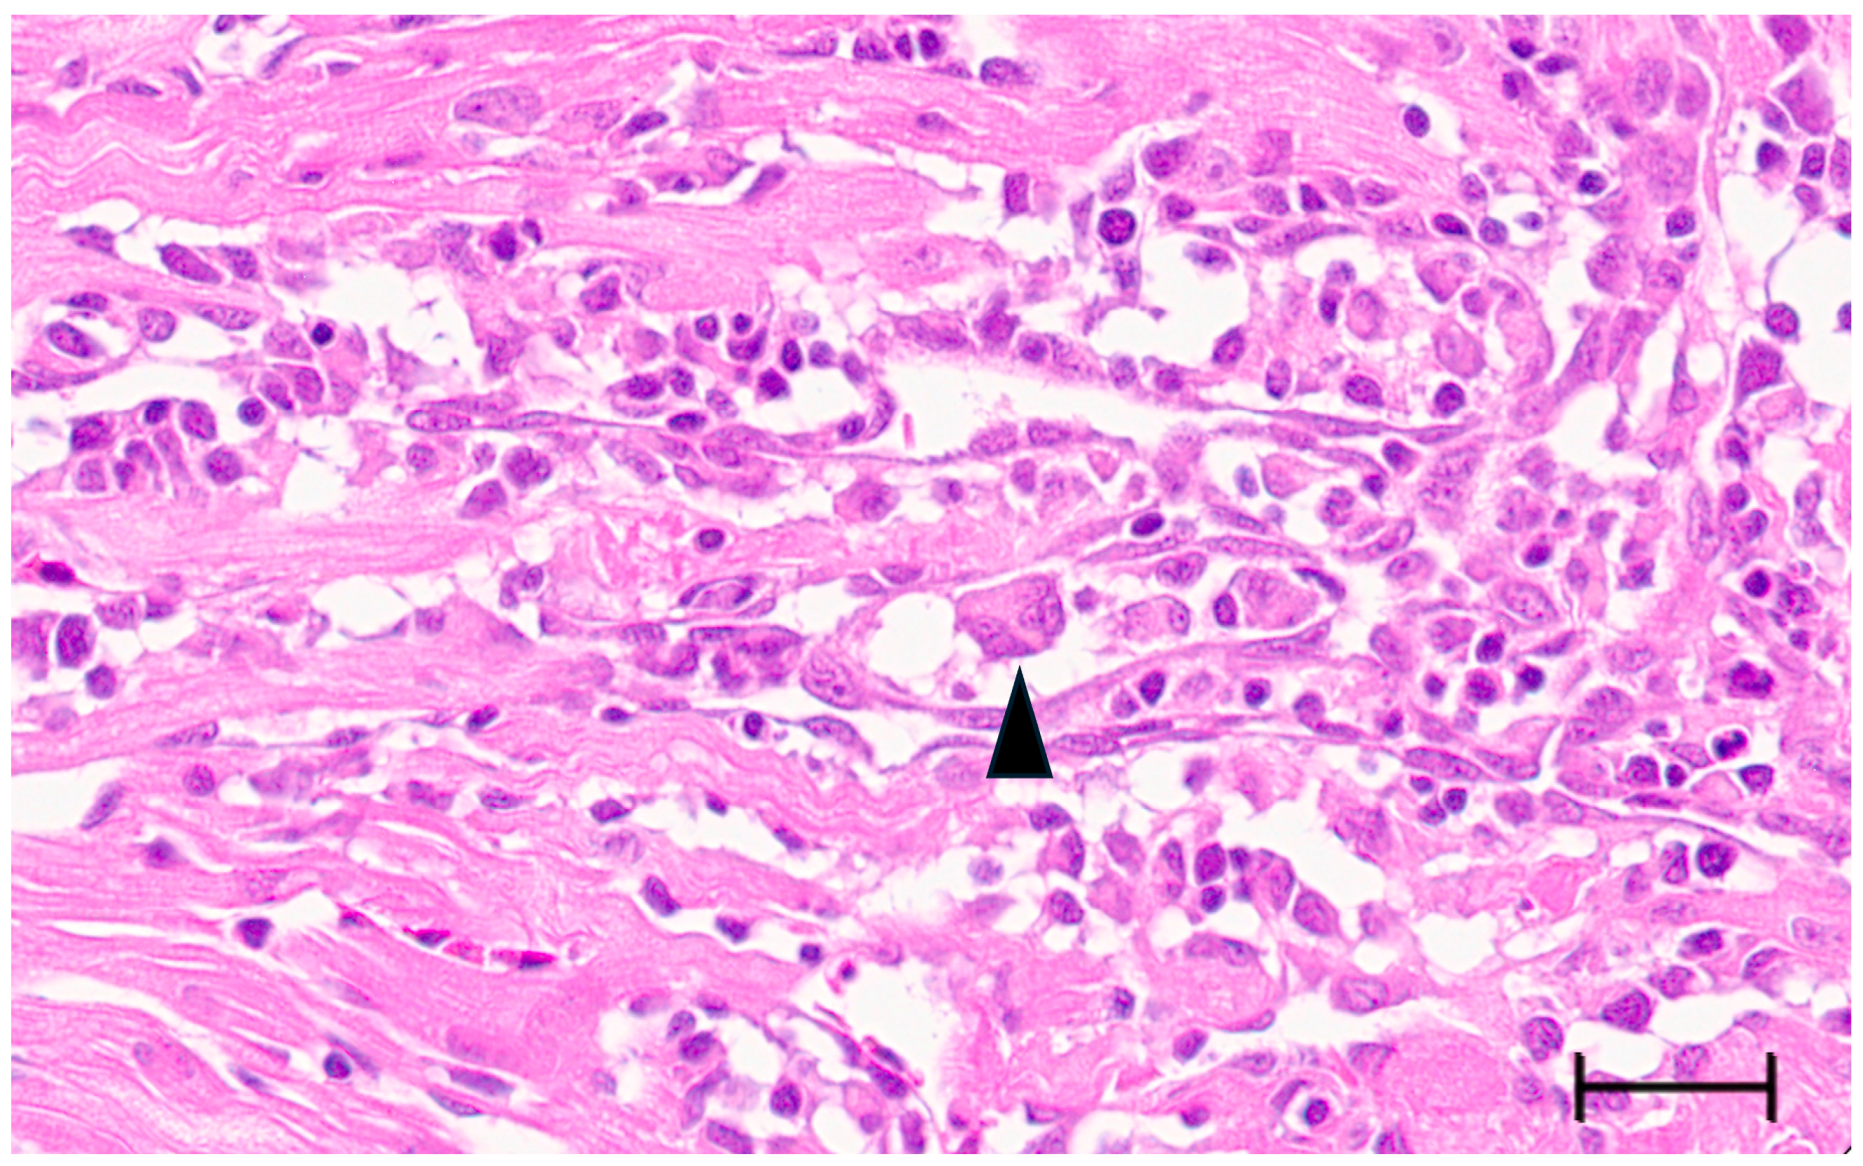

3.3. Multinucleated Cells Indicative of Cell Fusion Are Found Correlated with SBTLV Infection In Vitro and PMCV In Vivo, Supporting Presence of Functional FAST Proteins